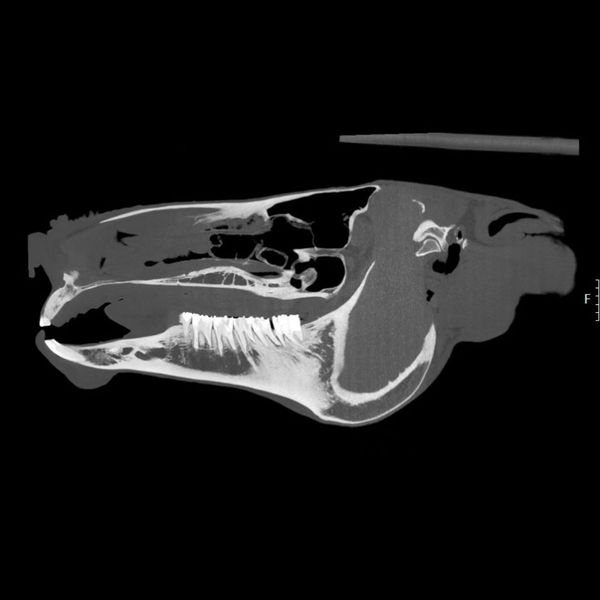

Hard Tissue Mastery: Digital Radiography for Horses

When we need to look at the "scaffolding" of your horse, we turn to digital radiography for horses. This technology is the gold standard for evaluating bones. If you suspect a fracture, or if your horse is showing signs of chronic lameness, X-rays allow us to see structural changes clearly. It is particularly effective for identifying equine bone spurs on X-ray, as well as osteoarthritis or developmental orthopedic diseases. Because our system is digital, we can capture high-resolution images right in the barn or clinic, providing instant feedback on your horse's skeletal health.